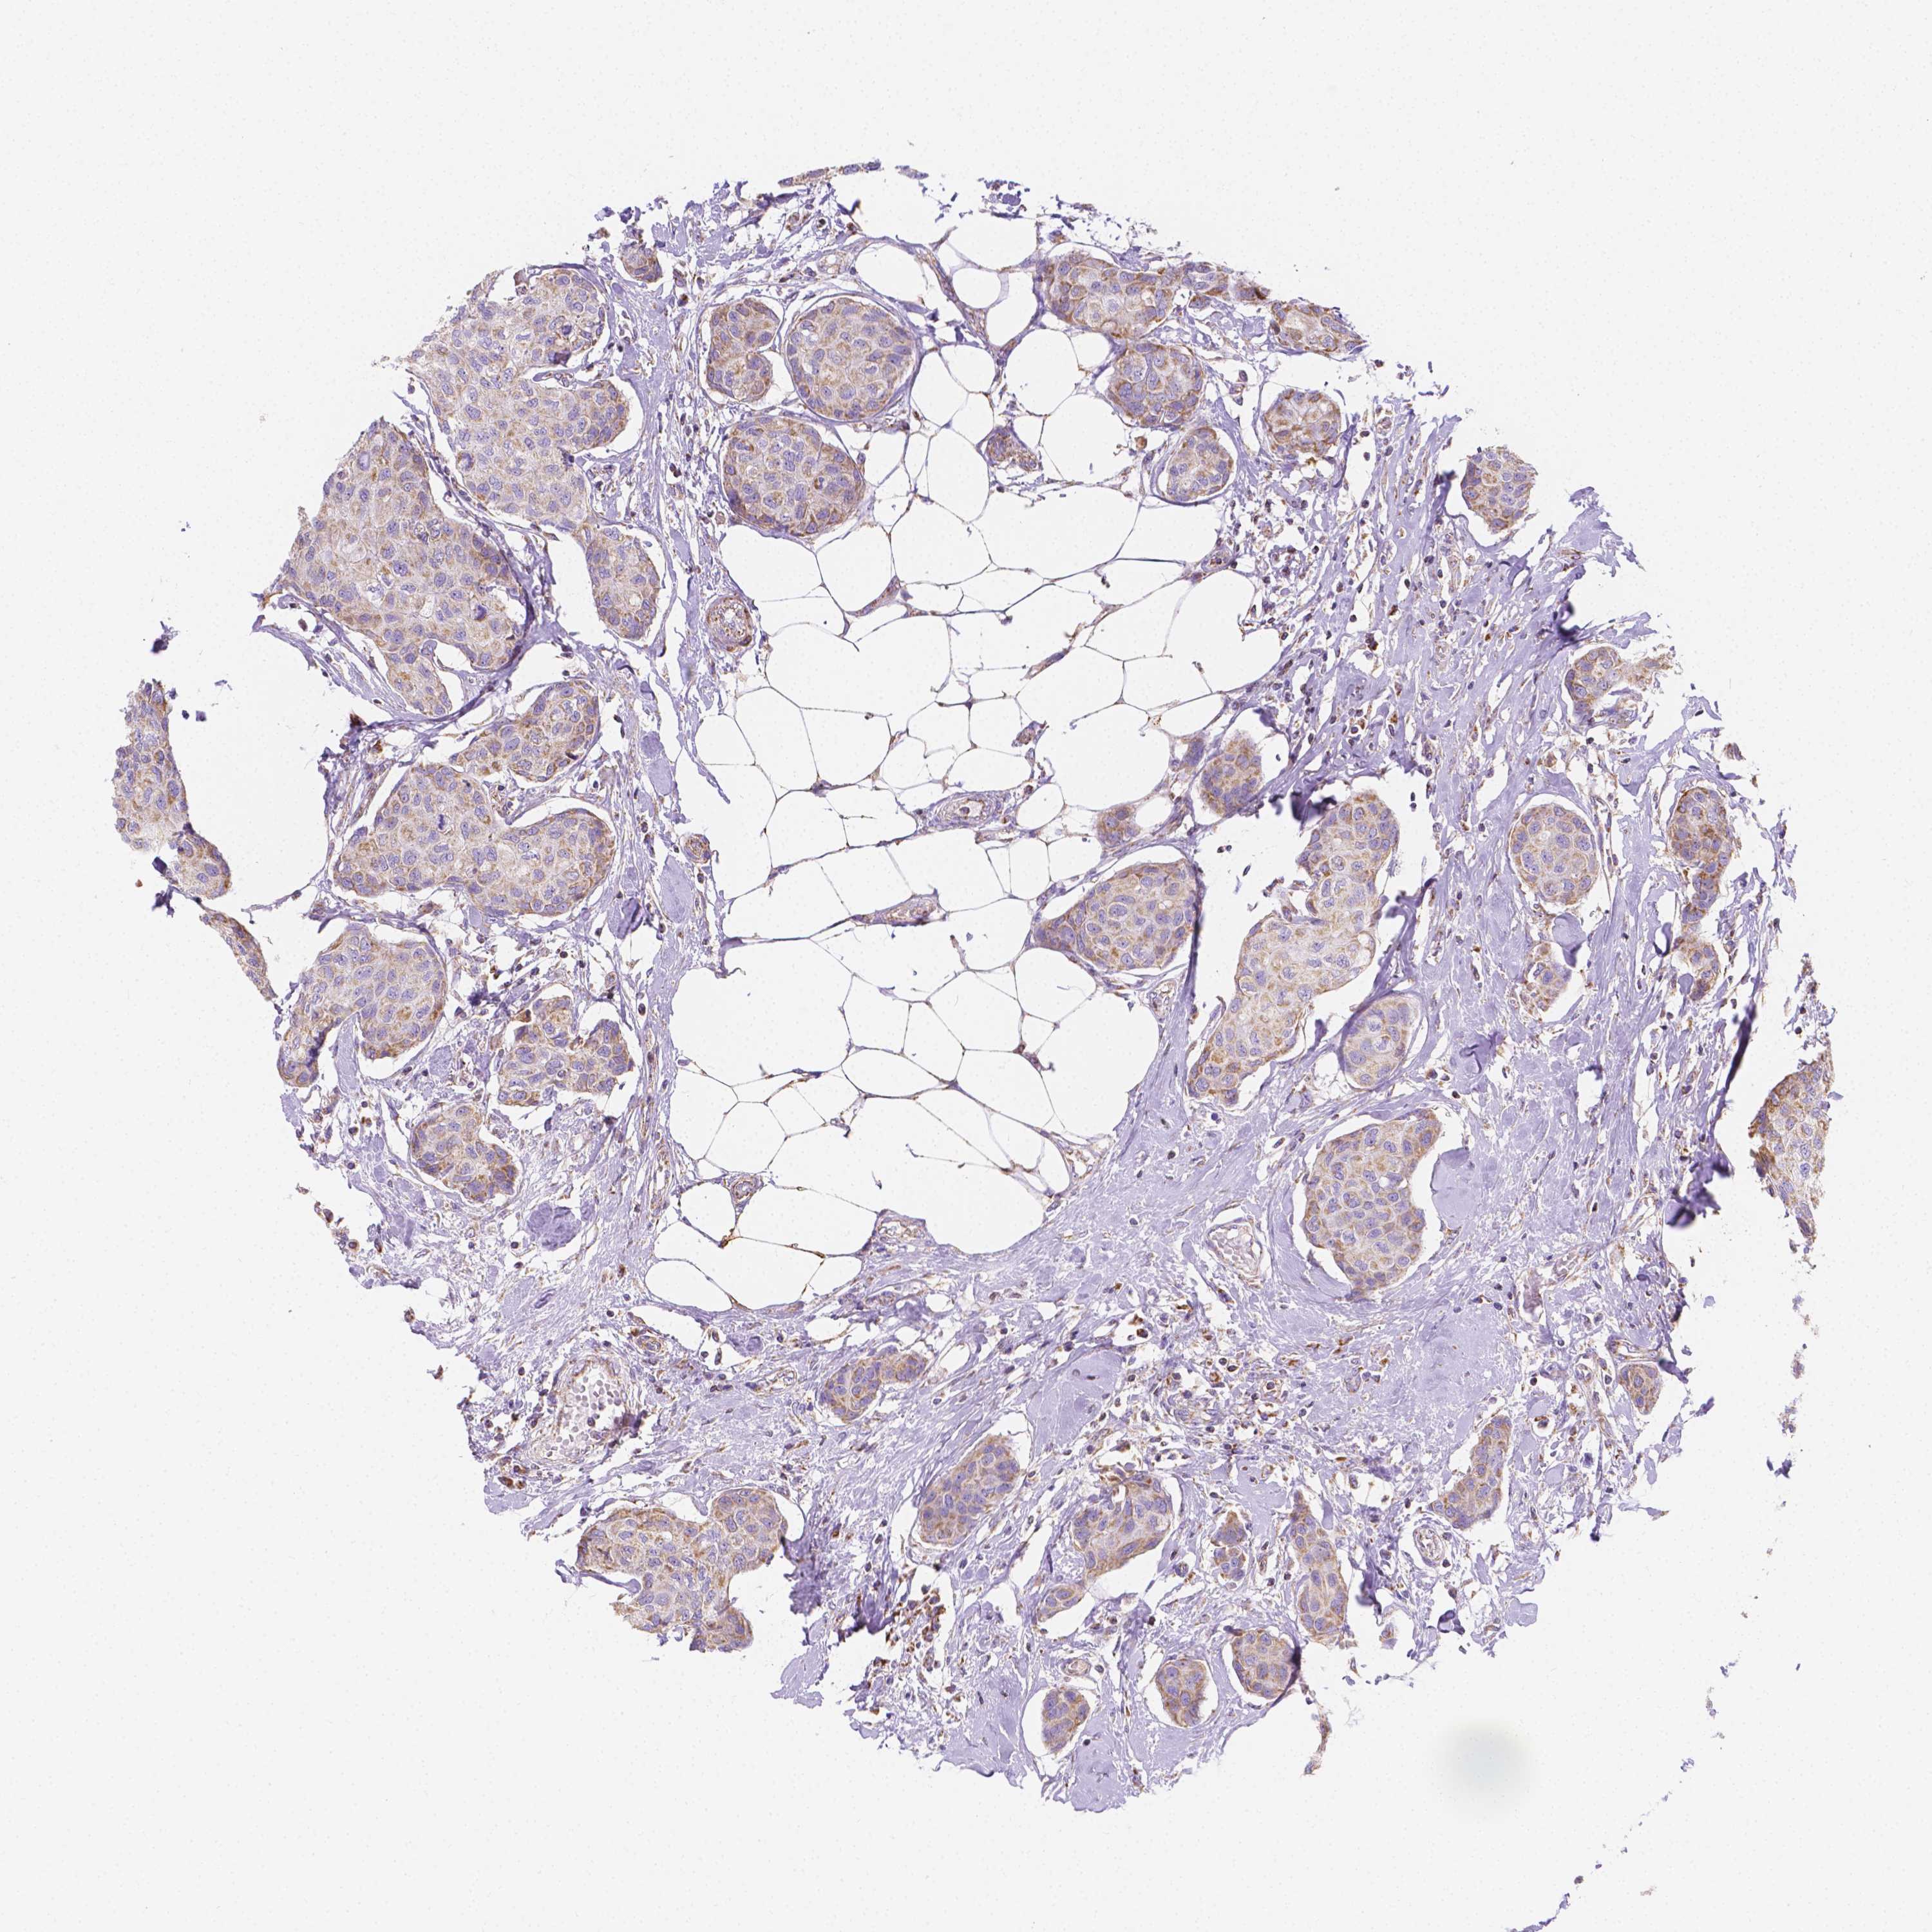

CANCER BREAST CANCER Show tissue menu

BRCA TCGA BRCA VALIDATION PROTEIN EXPRESSION

ANTIBODIES